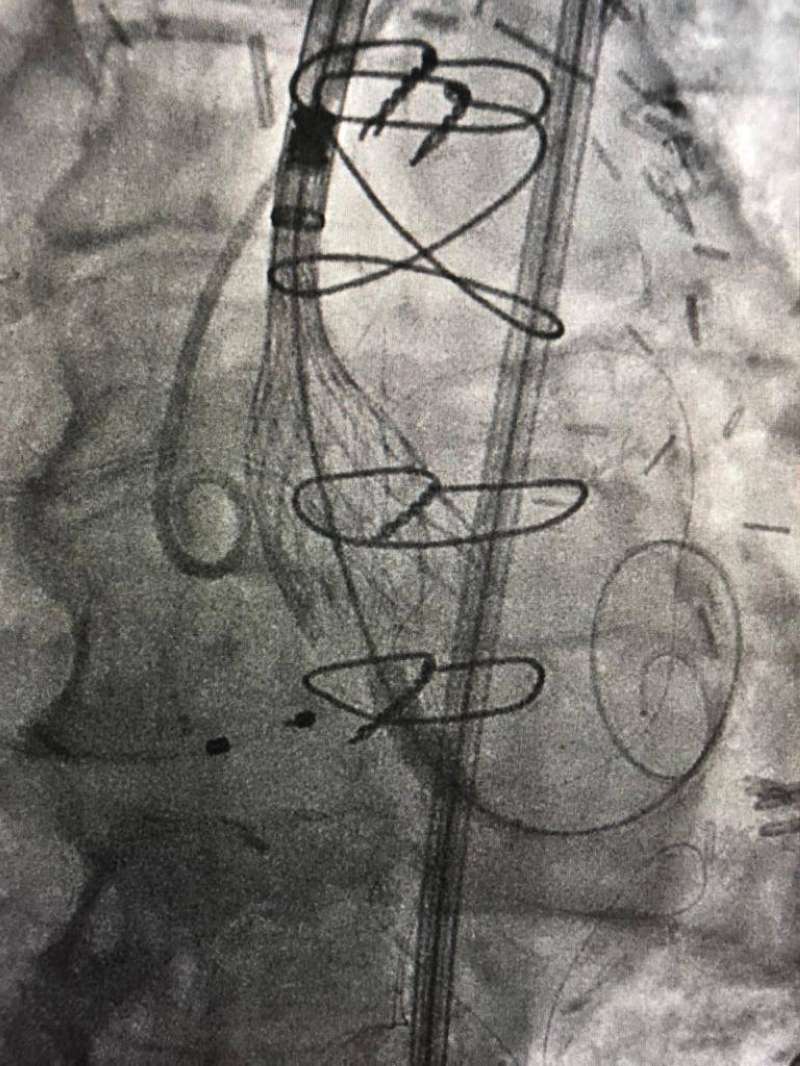

في إنجاز طبي غير مسبوق بدولة الكويت ووسط اجراءات طبية دقيقة نجح فريق طبي في مركز صباح الأحمد للقلب يضم استشاري القلب الدكتور نادر عيسى العسعوسي واختصاصي أول قلب الدكتور أحمد سعيد طه في إجراء عملية تبديل صمام أورطي (TAVI) عن طريق القسطرة لمريض يبلغ من العمر 101 سنة.

ويعتبر ما حدث إنجازاً غير مسبوق ليس من حيث درجة تعقيد العملية أو عمر المريض المتقدم ولكن لإجراء تبديل الصمام بدون استخدام صبغة للحفاظ على وظائف الكلى وهو ما يمثل أيضا اجراء طبيا غير مسبوق، حيث يتم في مثل هذه الحالات استخدام الصبغة لتسهيل إجراء عملية تبديل الصمام التي زاد من درجة صعوبتها و تعقيدها معاناة المريض من ضيق شديد بالصمام الأورطي وفشل عضلة القلب وقصور مزمن بشرايين القلب ووظائف الكلي، وتمدد بالشريان الأبهر في منطقة البطن (abdominal aortic aneurysm with mural thrombus).

وقد استغرقت العملية نحو ساعة وسط إجراءات طبية دقيقة بالنظر لظروف الحالة وتحدياتها بالغة التعقيد؛ حيث بذل فيها الفريق الطبي جهوداً تستحق التقدير وجديرة الثناء، وقد تماثل المريض للشفاء وأصبح بحالة جيدة مستقرة.